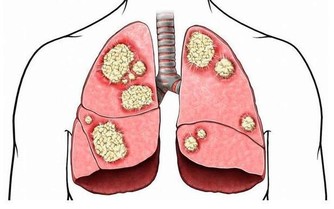

中醫師黃慧娟指出,造成痛風的主要原因為民眾經常食用高普林(Purine)食物,

像是海鮮、動物內臟、豆類等,促使體內尿酸過高,造成新陳代謝異常,

進而形成尿酸鹽結晶,沉積在關節內,造成關節疼痛及腫脹。